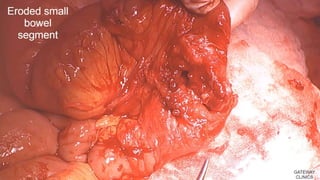

Against polypropylene mesh:

polypropylene without causing enterotomies*

• Major complications with polypropylene not evident

until years later

• 9 cases of mesh erosion fistula stainless steel (1)

tantalum (1) mersilene (1) dexon (1) ppm (5).

The time to the development of these fistulas

ranged from 3 months to 14 years

*Losanoff JE et al. Entero-colocutaneous fistula: a late consequence of polypropylene mesh

abdominal wall repair: case report and review of the literature, Hernia 2002; 6: 144-147